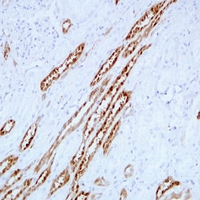

(Immunohistochemical analysis of PGP9.5 staining in human kidney formalin fixed paraffin embedded tissue section. The section was pre-treated using heat mediated antigen retrieval with sodium citrate buffer (pH 6.0). The section was then incubated with the antibody at room temperature and detected using an HRP conjugated compact polymer system. DAB was used as the chromogen. The section was then counterstained with haematoxylin and mounted with DPX.)